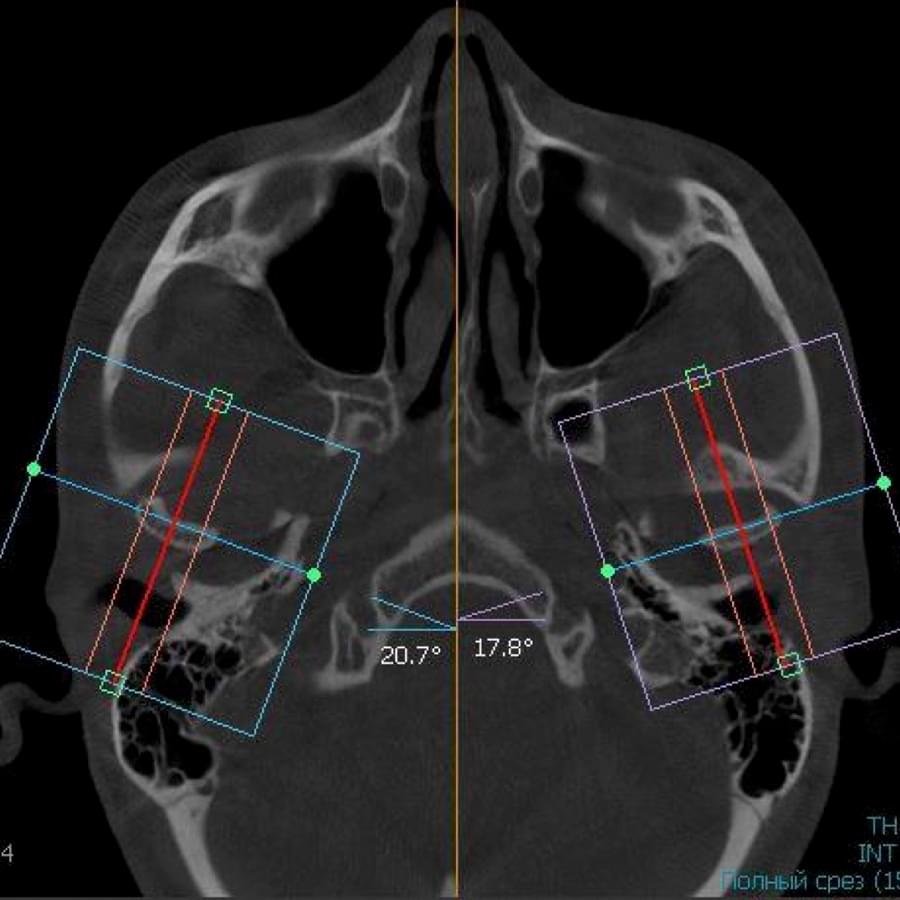

3D цефалометричний аналіз є сучасною технологією, яка дозволяє отримувати точніші,

комплексніші та надійніші дані про зубну та скелетну структуру. Ця технологія може стати

великим кроком в перед для ортодонтів, які хочуть забезпечити найкраще можливе лікування

своїх пацієнтів.

Точність: 3D цефалометричний аналіз забезпечує точніше визначення розмірів та відстаней між

зубами та кістковими структурами.

Комплексність: ця технологія дозволяє отримувати детальні дані про різні структури, такі як

кістка та м'язи, що дозволяє ортодонтам докладніше досліджувати деякі патології та планувати

лікування.